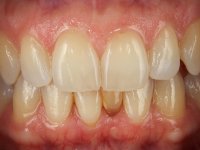

The deciduous tooth was extracted and a provisional resin crown with two small wings was bonded to the lingual surfaces of adjacent teeth. Two months later, the provisional crown was removed and the proximal walls were slightly prepared in order to parallelize the proximal walls and slight augment the mesio-distal space. After this minimal invasive dentistry, a dental impression was done with addition silicones in a one-stage technique. A provisional resin crown with an orthodontic wire on the buccal surface was then bonded to the adjacent teeth with resin, avoiding changing the prepared proximal and lingual surfaces.

In the dental lab, a Maryland bridge with a zirconia framework veneered with a feldspathic ceramic was built. The wings internal surface also had a very thin coating of a zirconia adhesive to allow its bonding to the abutments enamel. This Maryland bridge tried to join the mechanical strength of the framework, to the bonding of the ceramic to the enamel, and to the aesthetics’ of the zirconia’s veneering with a feldspathic ceramic.

Then, this Maryland bridge was bonded to the abutments.

This rehabilitation proved to be a minimal invasive procedure, affordable and aesthetically acceptable.